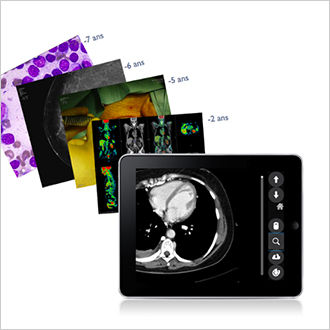

TM-MACS

Le MACS (Multimedia Archiving and Communication System) a pour objectif d’accompagner la tendance à la numérisation des départements et activités cliniques. La solution multimédia s’étend à tous les autres départements cliniques (ophtalmologie, dermatologie, cardiologie, bloc opératoire, urgences, anatomie pathologique, etc.). Telemis prend en charge tous les formats d’images, DICOM ou non-DICOM. Les cliniciens ont accès aux images et vidéos des dossiers patients, peuvent les visualiser et effectuer des diagnostics. Des outils d’analyse et d’affichage (zoom, loupe, annotations, mesure de distance, etc.) sont disponibles en vue d'améliorer les diagnostics. L’utilisation de labels permet de constituer des groupes d’examens et d’y accéder au moyen d’un simple clic. Un système de recherche personnalisée permet de retrouver le dossier du patient ou l'examen désiré de manière très rapide.